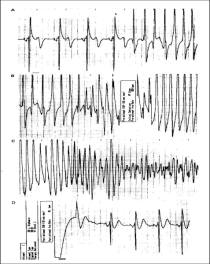

Defibrillators (ICDs) are useful in people who seem to be at risk from a life threatening arrhythmia. The device works as a pacemaker if required but can also deliver a shock to the heart if the rhythm should degenerate, restoring normal rhythm.

ICDs are implanted both for those who have suffered a serious arrhythmia and recovered and for those who seem to be at risk of serious arrhythmias in the future.